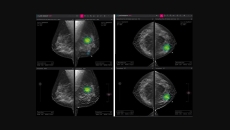

Also, Lunit signed multiple contracts this week to deliver its AI imaging software in Hong Kong, Mongolia, and Brazil.